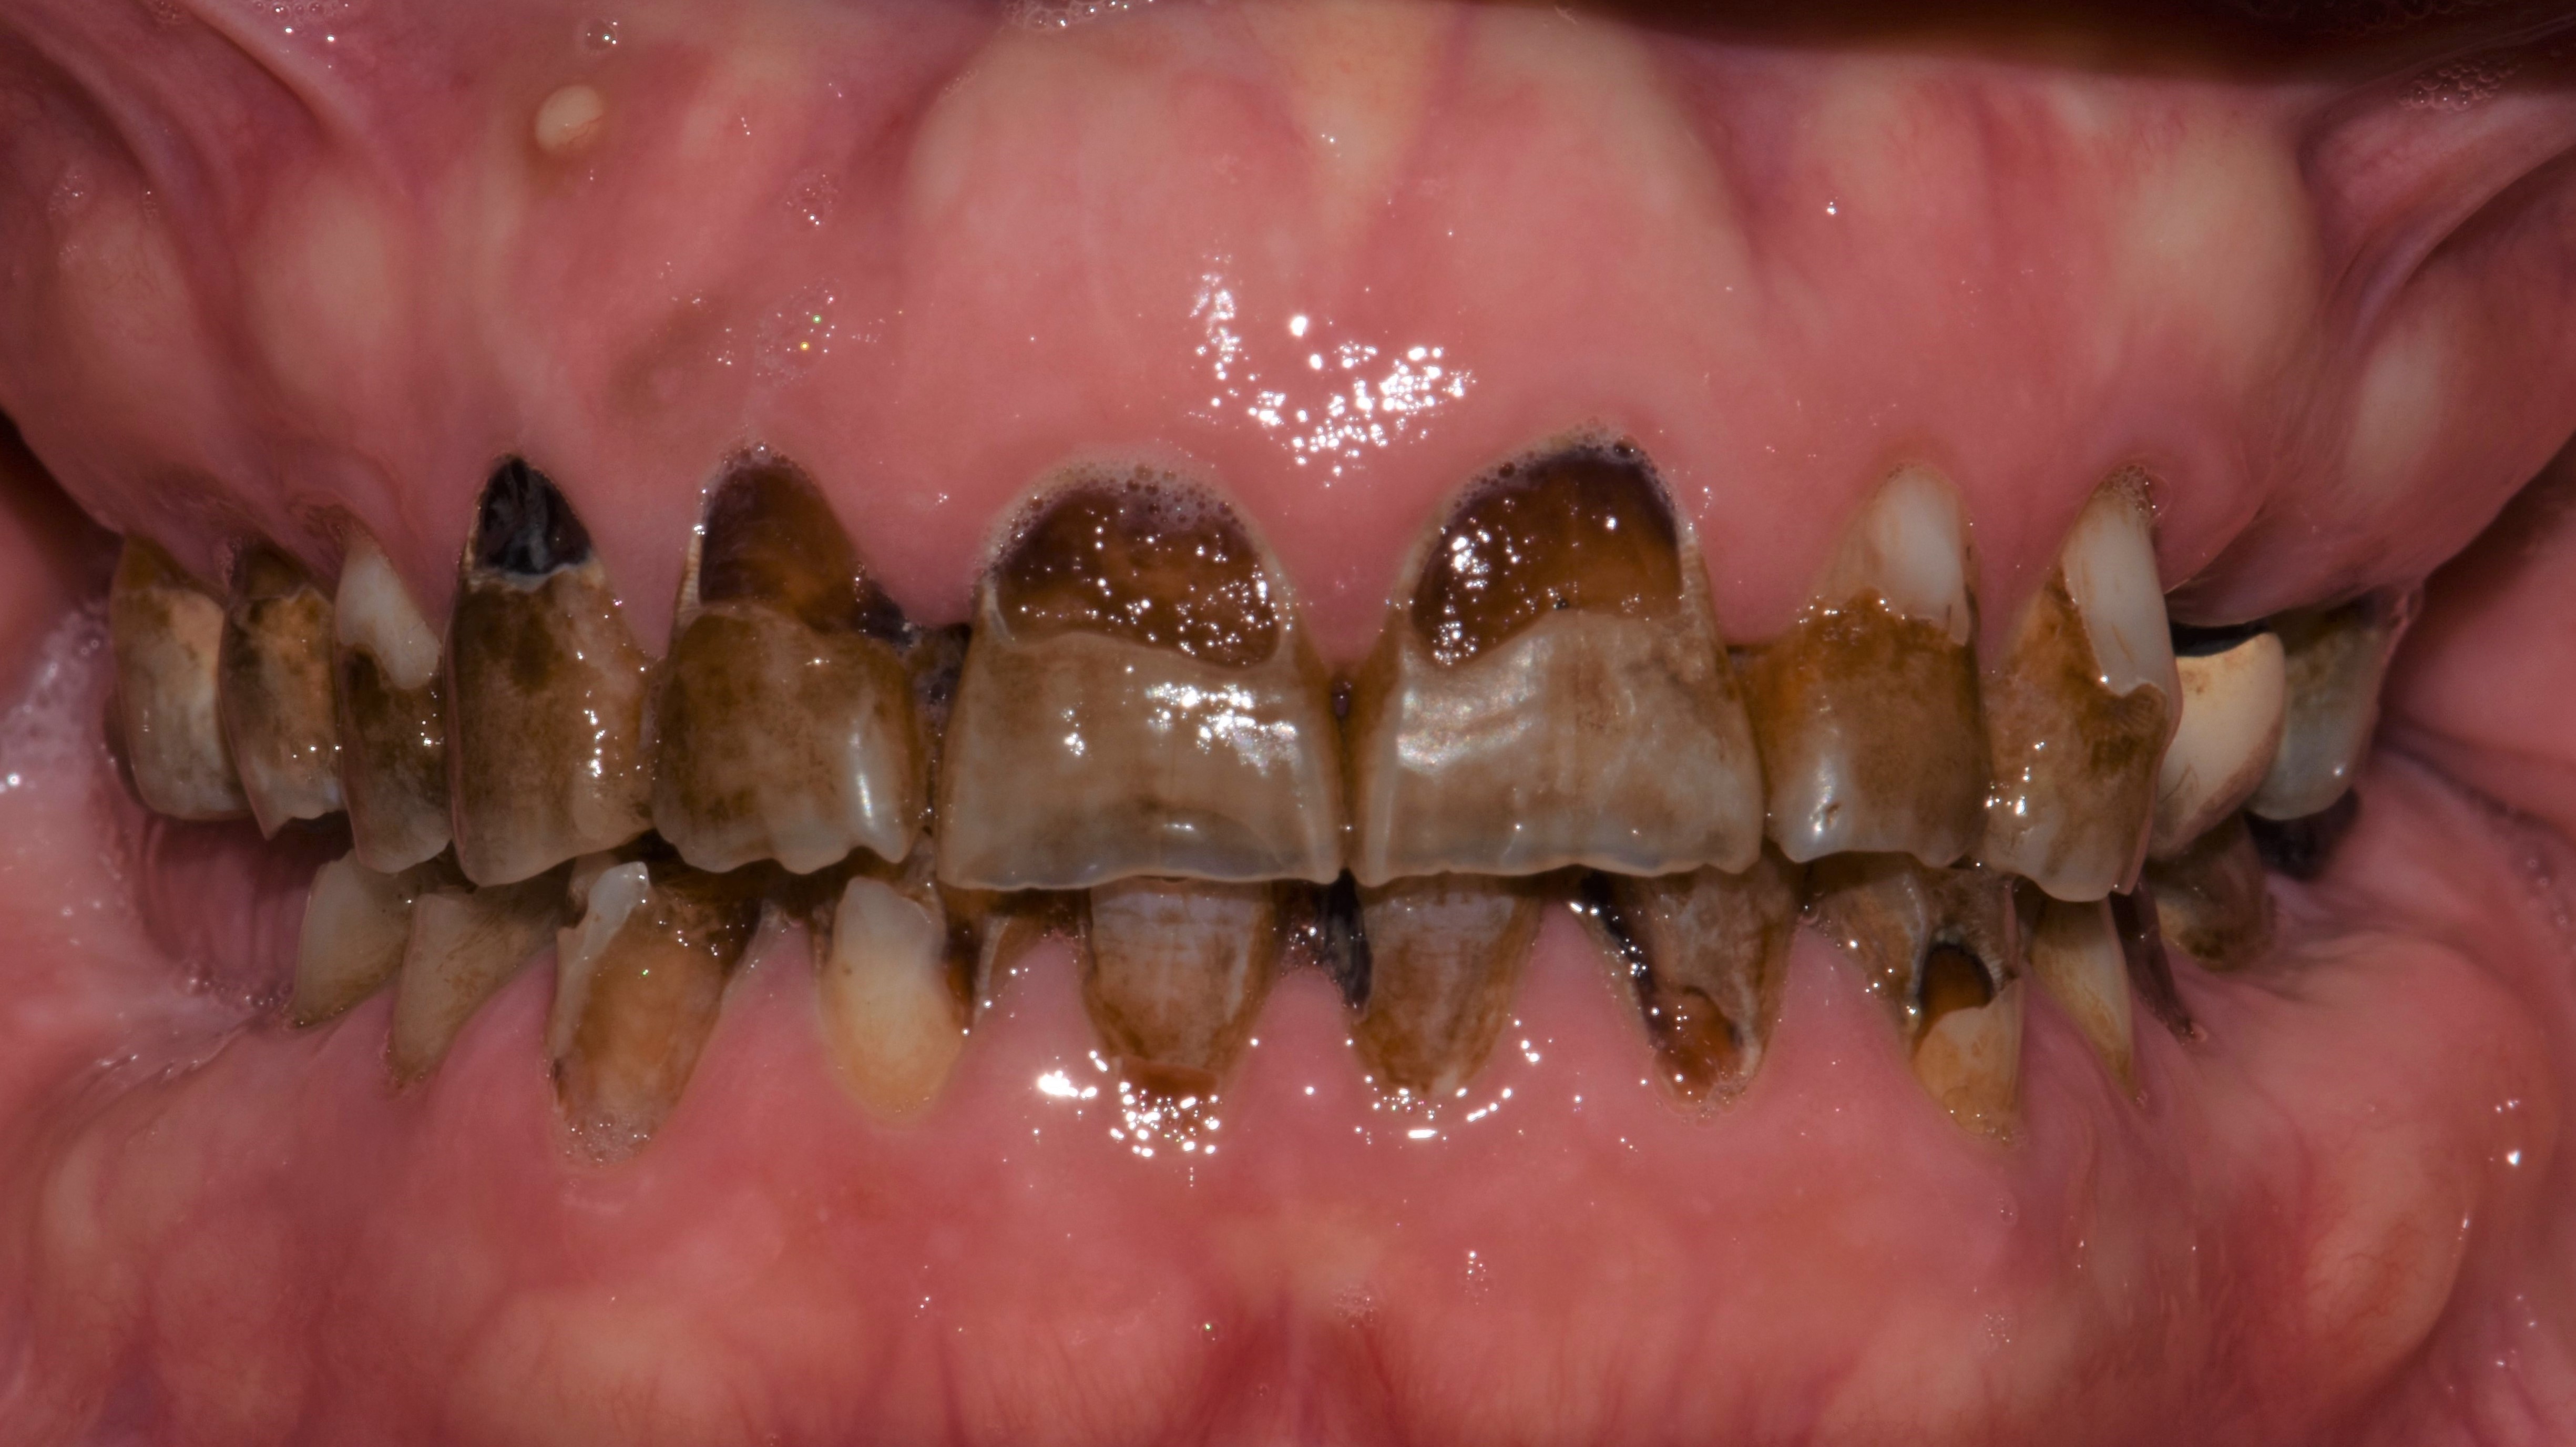

At a clinic treating patients in an underserved population, a 54-year-old female patient presented requesting extraction of all of her teeth and fabrication of dentures for her long-term restorations. The patient had a history of breast cancer, which had been treated with chemotherapy. She believed that full dentures would be an appropriate treatment option for her, owing to the poor state of her oral health and dentition and because she had limited financial resources and did not think that she could afford restoration of her teeth. The patient reported that she had experienced depression and alcohol abuse because of her cancer diagnosis, and that she had neglected her dental care during the course of her cancer treatment, resulting in generalized moderate-to-severe caries with moderate wear due to bruxism (Figure 1 through Figure 5). She also presented with significant staining of her remaining dentition due to the alcohol abuse.

Fig. 1